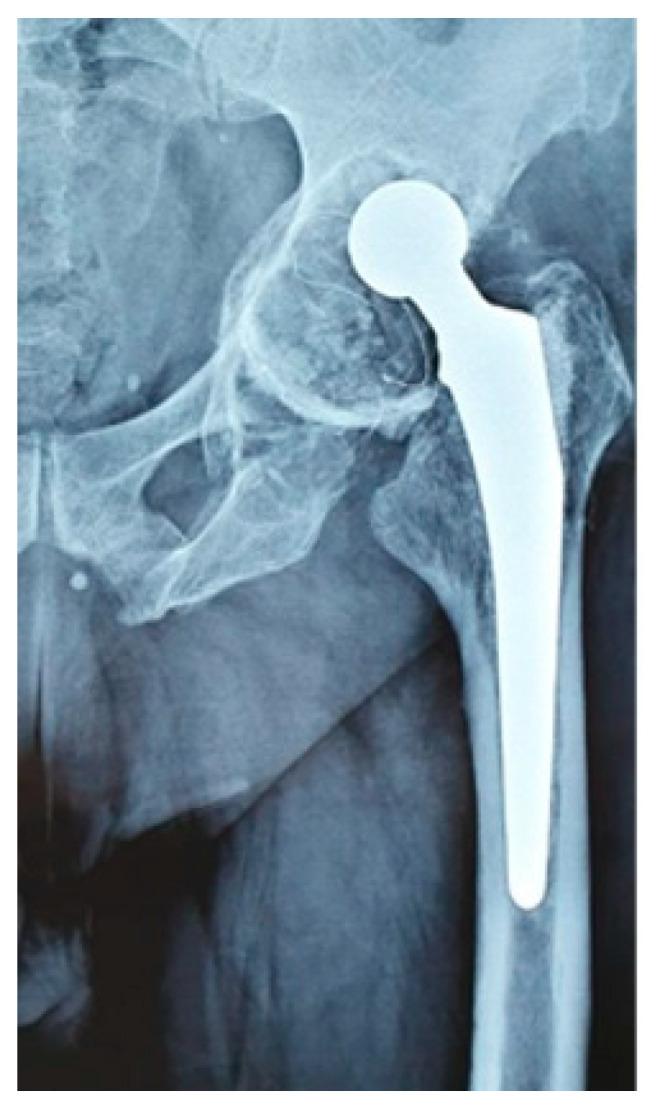

To reduce the incidence of total hip revisions, there have been continuous efforts to enhance prosthetic materials and designs to optimize implant survival. A primary implant with a constrained acetabular component is often used to minimize the risk of dislocations even though this approach has some drawbacks as reported in the literature. To address these concerns, this study aimed to assess the survivorship and dislocation rate of a semi-retentive cemented acetabular cup when used as a primary implant. The specific cemented cup that we studied was not present in any study that we consulted, so to fill this gap, we conducted a retrospective examination of 527 cemented hip prostheses that utilized the semi-retentive cup between the years 2005 and 2012. We employed Cox multiple regression models for our statistical analysis. The revision due to dislocation occurred in 12.8% of all cases, with a lower incidence of 5% (14 cases) in age groups >70 years than in age groups <70 years (14%-32 cases) ( < 0.001). The survival rates of the semi-retentive cemented acetabular cup were 98.6% (520 cases) at 5 years and 92.2% (487 cases) at 10 years. The survival rates were significantly lower in women than men, with 1.9% (7 cases) toward 0% at 5 years and 8.1% (30 cases) toward 5% (7 cases) at 10 years ( = 0.002). The difference in failure rates between age groups over 70 years (2.3%-10 cases) and age groups under 70 years (11.5%-34 cases) was also statistically significant ( < 0.001). Our study indicates that the semi-constrained design may cause frequent damage to the polyethylene liner due to impingement and wear, which are the primary factors for failure. Also, this implant has a similar risk of revision due to dislocation as reported in studies and may be beneficial as a primary implant in elderly patients with low-demanding lifestyles, muscular insufficiency, and low compliance regarding hip prosthetic behavior, without a major effect on survivorship.

为降低全髋关节翻修的发生率,人们不断努力改进假体材料和设计,以优化植入物的使用寿命。尽管文献报道这种方法存在一些缺点,但带有受限髋臼组件的初次植入物常被用于将脱位风险降至最低。为解决这些问题,本研究旨在评估半固定式骨水泥髋臼杯作为初次植入物时的生存率和脱位率。我们研究的特定骨水泥杯在我们查阅的任何研究中均未出现,因此为填补这一空白,我们对2005年至2012年间使用半固定式杯的527例骨水泥髋关节假体进行了回顾性检查。我们采用Cox多元回归模型进行统计分析。所有病例中因脱位导致的翻修发生率为12.8%,年龄>70岁组的发生率为5%(14例),低于年龄<70岁组(14% - 32例)(<0.001)。半固定式骨水泥髋臼杯的5年生存率为98.6%(520例),10年生存率为92.2%(487例)。女性的生存率显著低于男性,5年时从1.9%(7例)降至0%,10年时从8.1%(30例)降至5%(7例)(=0.002)。70岁以上年龄组(2.3% - 10例)和70岁以下年龄组(11.5% - 34例)的失败率差异也具有统计学意义(<0.001)。我们的研究表明,半约束设计可能会因撞击和磨损而频繁损坏聚乙烯内衬,这是失败的主要因素。此外,这种植入物因脱位导致翻修的风险与研究报道相似,对于生活需求低、肌肉功能不全且对髋关节假体行为依从性低的老年患者,作为初次植入物可能有益,且对生存率无重大影响。